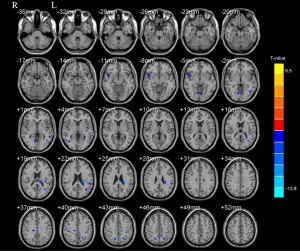

Results of volume comparison

Compared with the beginning of methadone treatment, the volume of GM in some brain areas of MMT patients decreased after 1 year of maintenance treatment. Areas affected were mainly in the bilateral insular lobe, occipital lingual gyrus, right cingulate gyrus, superior temporal gyrus, left inferior parietal lobule, caudate nucleus, middle temporal gyrus, and middle occipital gyrus (FDR correction, P<0.01). No increased GM volume was seen in any brain area (Table 3, Figure 1).

Table 3

| Brain area | BA | L/R | MNI coordinates |

|

Clusters | ||

|---|---|---|---|---|---|---|---|

| x | y | z | |||||

| Insular | 13 | R | 44 | 11 | −6 | −9.33 | 201 |

| Occipital lingual gyrus | 18 | R | 12 | −68 | −3 | −7.83 | 136 |

| Superior temporal gyrus | 22 | R | 57 | −44 | 3 | −9.64 | 50 |

| Posterior cingulate gyrus | 31 | R | 15 | −27 | 38 | −7.77 | 113 |

| Occipital lingual gyrus | 18 | L | −6 | −71 | −3 | −7.41 | 88 |

| Fusiform gyrus | 37 | L | −42 | −62 | −14 | −7.26 | 76 |

| Inferior parietal lobule | 40 | L | −54 | −35 | 27 | −9.15 | 178 |

| Insular | 13 | L | −42 | −2 | 3 | −7.42 | 76 |

| Occipital gyrus | – | L | −33 | −63 | 18 | −8.98 | 145 |

| Caudate | – | L | −26 | −29 | 24 | −14.13 | 366 |

MMT, methadone maintenance treatment; BA, Brodmann area; L, left; R, right.